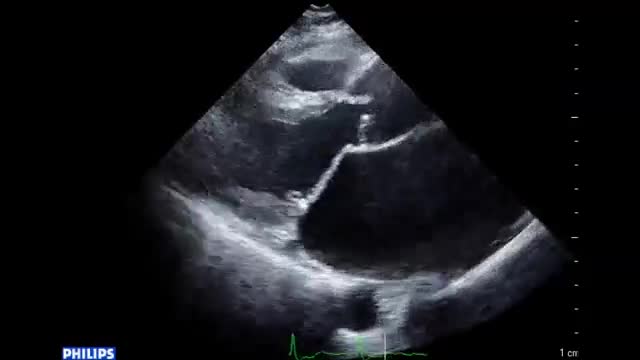

• 症例2 60代男性.僧帽弁逆流症

• 図2 心尖拍動 a

• 図2 心尖拍動 b